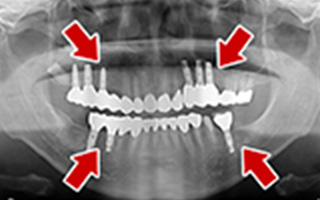

Before

After

| 68歳 男性 | 紹介 |

|---|---|

| 主訴 | れ歯が合わない 食べにくい 人生を豊かにしたい |

| 処置内容 |

上顎4本で12歯(オールオン4)、下顎4本5歯 上下抜歯即時埋入、即時荷重(手術当日にインプラントの上に仮歯装着) |

| 治療費用 | 上顎: 約220万(税込) 下顎: 約180万円(税込) |

| 治療期間 | 上顎: 9ヶ月 下顎: 6ヶ月 |

| リスク |

術後の腫れ、痛み(ピークは3日後、1週間で軽減) 上部構造物、仮歯の破折、人工歯根脱落リスクがあります |